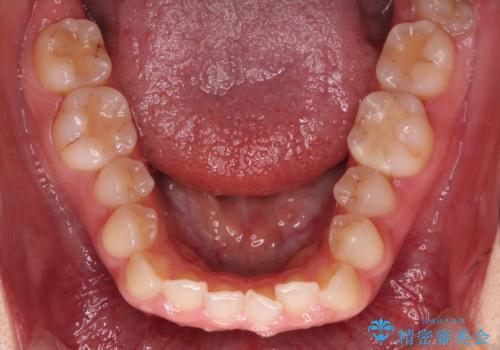

- 前歯の凸凹を主訴に来院された患者様です

骨格性の下顎前突傾向もあったため、臼歯関係の遠心移動も行うことで綺麗な仕上がりで矯正を終了することができました。

遠心移動を行うことで期間はかかりましたが、良い状態で仕上がっています。